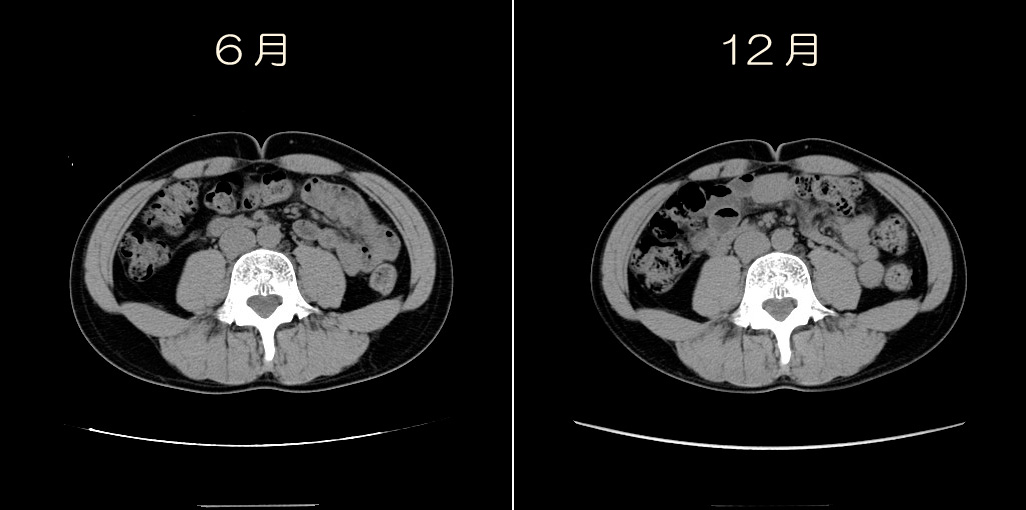

ではその「3cm」をCTで確認しましょうw。

おへそのあたりの部分です。

左が6月、右が今回の12月です。

わかりにくいので合成してみました。

おおお!!!

外側の線が6月、内側の線が12月。

背中側の脂肪が多めに減ったのか!!